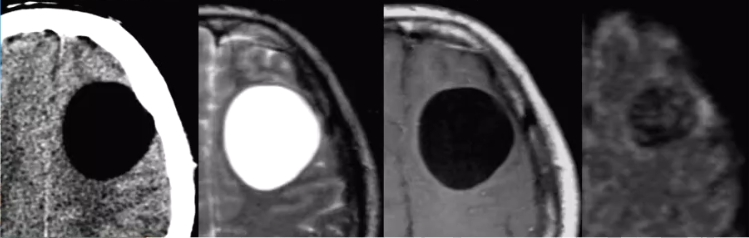

脑包虫病(echinococcosis)

>脑包虫病少见,仅占包虫病1%-2%;

>主要见于畜牧区,感染棘球绦虫的幼虫(棘球蚴)所致;

>多见于儿童、青少年,表现为癫痈、颅内压增高等;

>脑内多分两种—囊型(CE)、泡型包虫病(AE);

√CE—囊状,多见于大脑中动脉供血区;

√AE—具有侵袭性,患者有肝包虫病。